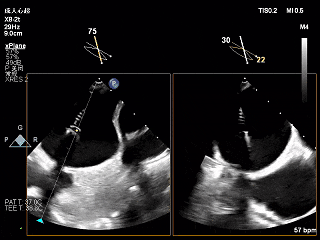

术前Bicom切面

术前X-Plane

术前瓣口面积5.39cm²

后叶长度9.24cm

可用房间隔穿刺高度4.03cm

3D-ZOOM 彩色多普勒显示反流主要来源于2区